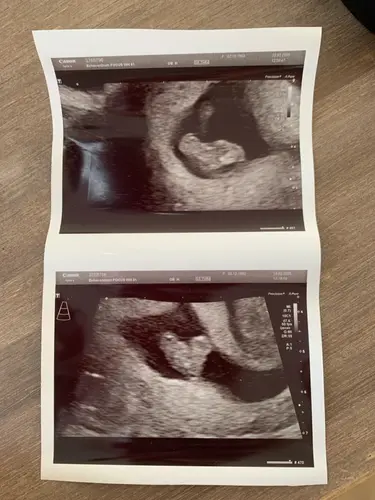

Daar is 'ie dan. Eigen berekening 7.5 weken, wordt nu geschat op 7.3 - 7.5 dus dat komt mooi overeen. Ik had in eerste instantie een uitwendige echo, maar er zat een waas over het beeld, dus we hebben daarna een inwendige gedaan. Heel blij met het beeld wat we toen zagen: een kloppend hartje ❤️.